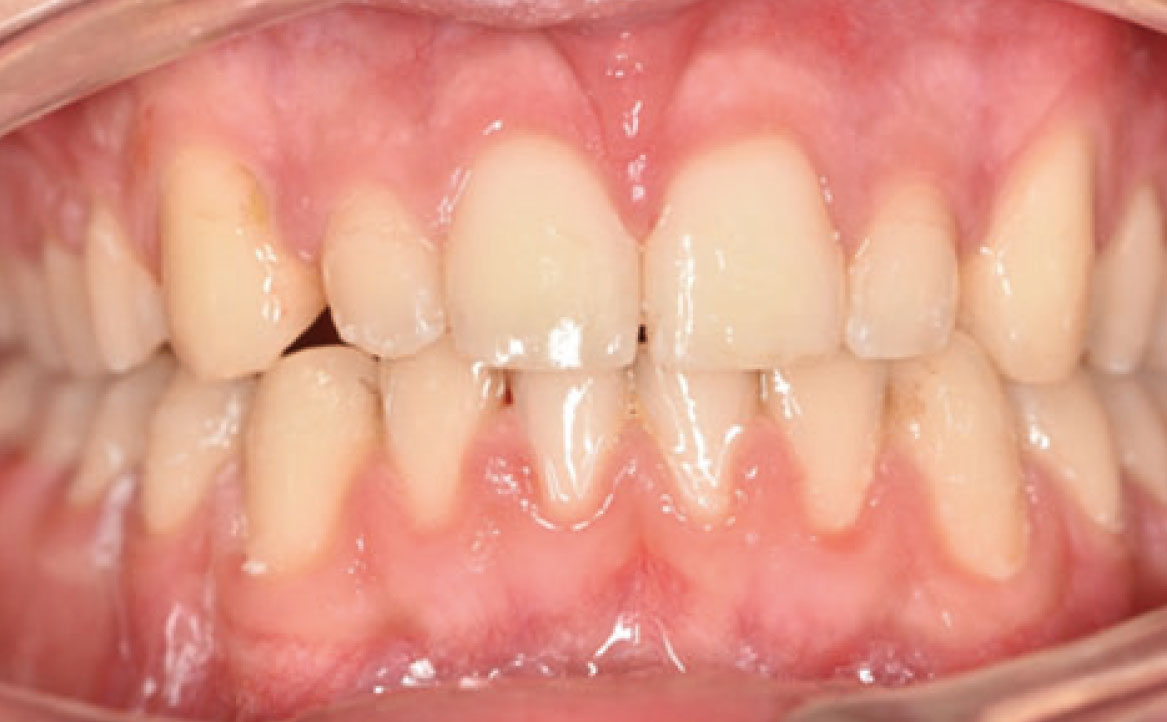

Il paziente è stato rivalutato circa 12 mesi dopo il debonding di entrambe le arcate con un OPT, al fine di valutare il rapporto tra le radici degli elementi dentali, le arcate dentarie, le ossa dei mascellari, i seni mascellari e la struttura ossea delle articolazioni temporo-mandibolari. Attraverso l’OPT è stato testimoniato che i risultati ottenuti con il trattamento ortodontico erano ancora altamente qualitativi sia dal punto di vista funzionale che estetico a 12 mesi dalla fine del trattamento (fig. 8a) e includevano: una classe I del primo molare e del canino, un allineamento degli elementi superiori e inferiori, una proclinazione degli incisivi superiori, un’apertura del morso e una lieve derotazione dei molari superiori.